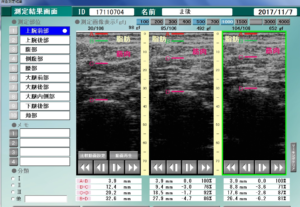

測定のプローブをグッと押し込んで、緩めてを繰り返します。

その時の組織のつぶれ具合が数字で表示されます。軟らかい組織は大きくつぶれます。

筋肉も柔軟性があれば押圧力で圧縮されますが、硬くなるとあまり変化しません。

(一番下の線が骨、その上が2層の筋肉。さらに上は脂肪層。)

(左から力を加えていきます。 どれが、一番軟らかい?)